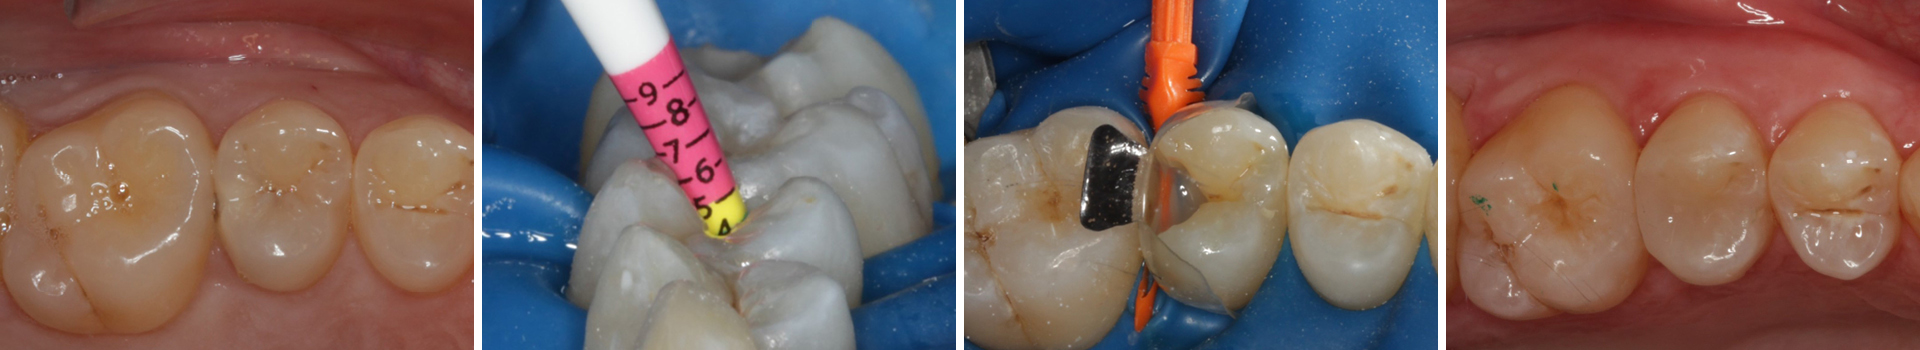

Behandlung einer tiefreichenden Karies an Zahn 25 distal

Tiefreichende kariöse Läsionen im distalen Bereich stellen häufig eine besondere Herausforderung dar, da sie sowohl eine präzise Kavitätenpräparation als auch eine anspruchsvolle Rekonstruktion der Kontaktpunkte erfordern. Durch Anwendung der Bioclear Evolve Matrizen konnten in diesem Fall eine ästhetisch und funktionell hochwertige Versorgung erzielt werden, die gleichzeitig minimalinvasiv und substanzschonend war.

Abbildung 1

Approximalraumkaries an Zahn 25 distal

Abbildung 5

Defektdarstellung

Matrize, Twinring, und Keil entfernt; weitere Lichthärtung von bukkal und oral

Abbildung 16

Überschussentfernung/ „Anpolieren“ u.a. trocken mit Sandpapierscheibe

Abbildung 17

Zahnseidenkontrolle: kein Überschuss, satter Kontaktpunkt

Abbildung 18

Fertige Restauration

Also ich kann jetzt für mich sagen, dass die neuen Evolve Matritzen nochmal ein richtiger Schritt nach vorn hinsichtlich Formstabilität, Kantensteifigkeit, und aber insbesondere der Behandlung extrem tiefreichender (approximaler) Defekte sind. Obwohl diese Matrizen angeblich so dick sind wie die Biofit-Matrizen, sind sie gefühlt dünner und dabei gleichzeitig stabiler. Ein Riesenvorteil bei tiefer Zerstörung ist diese zusätzliche "Lasche", mit der fast alle Defekte sauber eingefasst werden können.